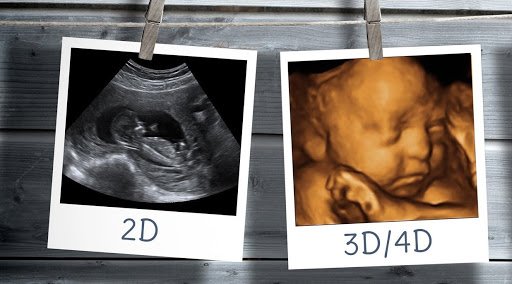

These are usually the 2D black and white scan images you are probably used to seeing in the hospital. This is because at this early stage baby isn’t yet developed enough to see in more detail. The same technology (ultrasound machine and probe) is used later in your pregnancy but is capable of showing you much more detail once your baby is sufficiently developed, usually this is possible from around 16 weeks but best images are taken around 27 weeks. These are the high detail 3D pictures that have a golden look and feel to them.

Image quality then drops off around 36 weeks because although baby is developing further there is less space for baby and fluid to help capture those pictures. 4D (sometimes referred to as ‘live’) is the same 2D or 3D image but a video capture of that examination that you can watch back at a later date. Our packages are available with scan only, scan plus picture images or scan plus picture images plus 4D video saved to a USB stick.